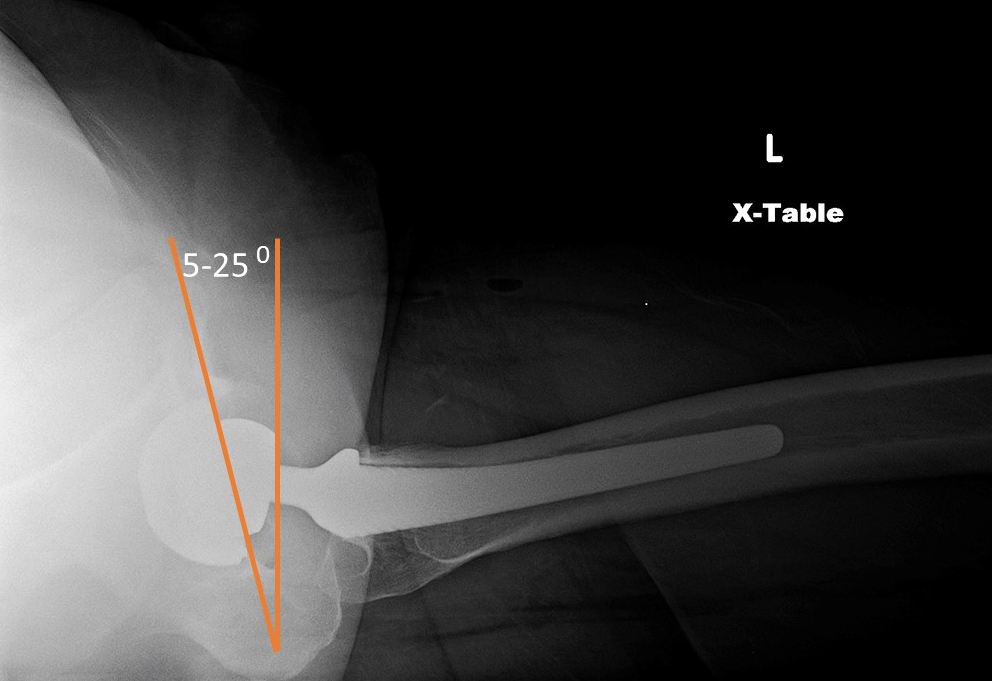

Anteversion of the acetabular component is evaluated on the true cross-table lateral radiograph of the hip with normal anteversion being 15-20°, although a range of 5-25° is considered normal. On a true lateral radiograph anteversion can only be truly qualitatively estimated. The apparent angulation is affected by pelvic or thigh rotation and the inherent limitations of cross-table lateral hip radiography. If more exacting measurement of anterversion is required, particularly measurement of femoral anteversion, it should be assessed with CT (Manaster, 1996; Mulcahy, 2012; Deshmukh, 2019).

38 year old man with bilateral THA for advanced osteoarthritis. On a true cross-table lateral view of the hip there is normally 5-25 degrees of anteversion which is measured as the angle between the rim of the acetabular cup and a line drawn perpendicular to the horizontal surface. |